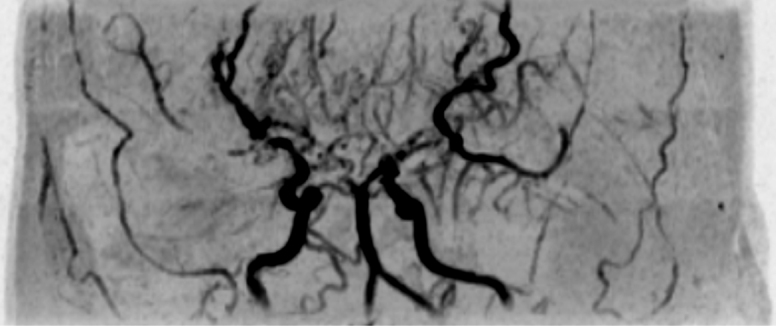

Moyamoya disease is a rare cerebrovascular occlusive disorder, and its natural course remains incompletely understood. Although rare, extracranial arterial lesions can develop in patients with moyamoya disease. We report the case of a 35-year-old Japanese woman with moyamoya disease who was referred to our department for the treatment of severe chronic mesenteric ischemia. She had a several-year history of postprandial abdominal pain and experienced two episodes of gastric ulcer perforation in the past year. Enhanced computed tomography revealed that the patient had a common trunk of the celiac and superior mesenteric arteries, which was occluded at its origin. The patient underwent an aorta to superior mesenteric artery bypass with a great saphenous vein graft. The postoperative period was uneventful, and the patient is now free of symptoms. The present case suggests that a patient with moyamoya disease can develop symptomatic mesenteric arterial lesions.